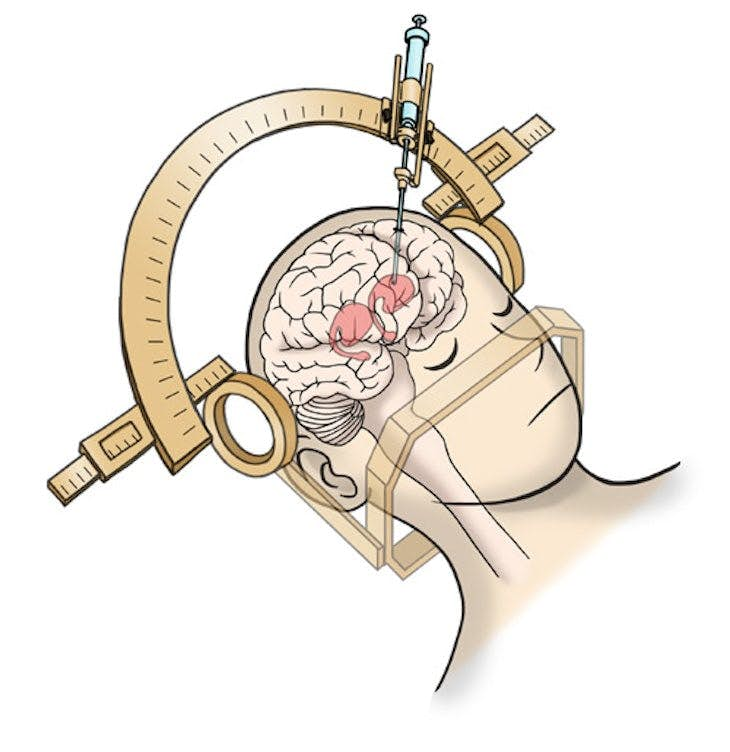

Parkinson'a karşı savaşmak

Parkinson hastalığı insan beyninde dopamin üretiminde düşüşe neden olur ve bu da bir hastanın motor becerilerini engeller.

2017'de yayınlanan Kyoto Üniversitesi'nden yapılan araştırmalar, hücrelerin dopamin nörotransmitterini oluşturmaktan sorumlu nöron olan dopaminerjik progenitörlere dönüştürülmesi yoluyla hastalıklı maymun beyinlerinde bu olasılığı araştırdı ve sonuç başarılı oldu.

Ardından yedi canlı Parkinson hastası deneğin her birinin özel bir cihazla beyinlerine nakledilen beş milyon İPKH türevli dopaminerjik progenitörünü gördü. Araştırmacılar bunların dopaminerjik nöronlar haline gelmesi ve hastalığın etkilerini azaltmasını umut ediyor. Denemeler geçen Ağustos ayında başladı ve hastalar bundan sonra iki yıl boyunca yakından gözlemleniyor.